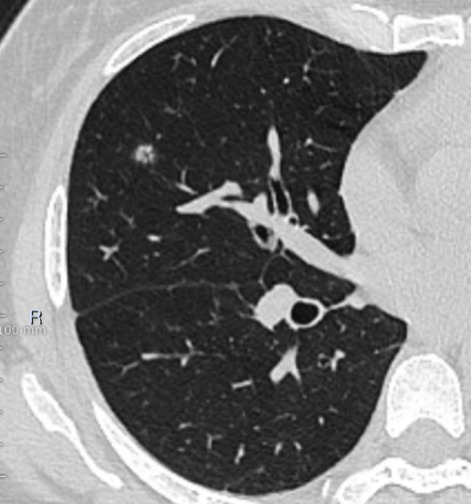

此次手术的主要目标——右中肺结节